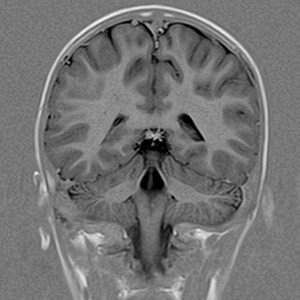

Ressonância Magnética De Alto Campo

É o método de diagnóstico por imagem mais moderno disponível no mercado, capaz de obter imagens de várias regiões do corpo com altíssima definição e resolução. É um exame inócuo, pois as imagens são obtidas através de campo magnético e pulsos de radiofrequência, não sendo necessária exposição a radiação ionizante.

Em alguns exames pode ser indicada a utilização de meio de contraste intravenoso. Nestes casos, o contraste usado chama-se o Gadolineo, que por não conter iodo, é muito seguro e raramente causa reações alérgicas ou sintomas.